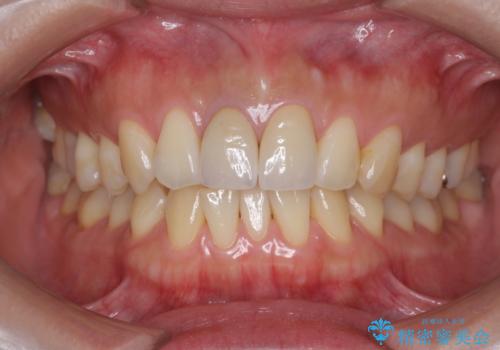

前歯の変色 根管治療と高品質セラミック歯科治療

- 前歯の変色の改善を求めて来院されました。

X線検査を行ったところ、共に深い虫歯が原因となり神経が死んでしまっている状態であることがわかり、根管治療を行ったのちセラミック補綴を行っていくこととなりました。

最終的なセラミッククラウンの精度・色調は非常に大事ですが、そこに至るまでの根管内環境の洗浄、ファイバーコアによる緊密な封鎖も長期的な予後に重要であると考えます。